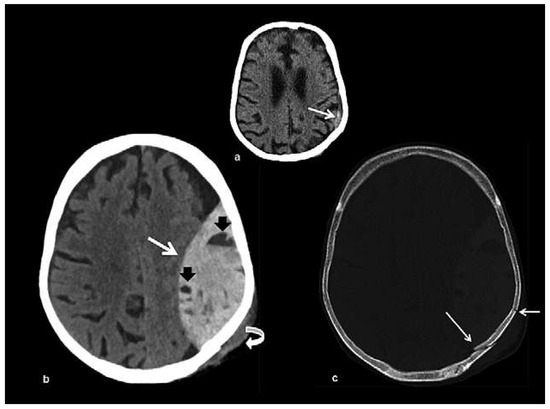

Head and brain trauma: general aspects and neuroimaging

by Johanna Maria Lieb, Christoph Stippich and Meritxell Garcia

In this article the general clinical aspects, imaging indications and different injury mechanisms of traumatic brain injury (TBI) are reviewed. In addition, the different imaging modalities and strategies are presented, including more specific imaging features of the various injuries. Computed tomography (CT) is [...] Read more.

In this article the general clinical aspects, imaging indications and different injury mechanisms of traumatic brain injury (TBI) are reviewed. In addition, the different imaging modalities and strategies are presented, including more specific imaging features of the various injuries. Computed tomography (CT) is the imaging modality of choice in the acute phase owing to its wide availability and short scanning time, as well as to its high sensitivity for the detection of fractures and acute bleeding. Although magnetic resonance imaging (MRI) is superior to CT in many other aspects, it plays no role in the acute phase. MRI, however, has been proven to be useful and complementary to CT in the subacute and chronic stages as well as in the case of inconclusive results on initial CT. Especially the use of standard sequences like fluid attenuated inversion recovery (FLAIR), diffusion and susceptibility weighted imaging (DWI and SWI) have been shown to increase the diagnostic potency in diffuse axonal injury, in mild brain trauma and also in more chronic stages of TBI. The use of more advanced MRI techniques such as diffusion tensor imaging (DTI), magnetic resonance spectroscopy (MRS), functional MRI (fMRI) and magnetic transfer imaging (MTI) can further complete the diagnostic evaluation and give insights into different pathophysiological processes in TBI. Full article